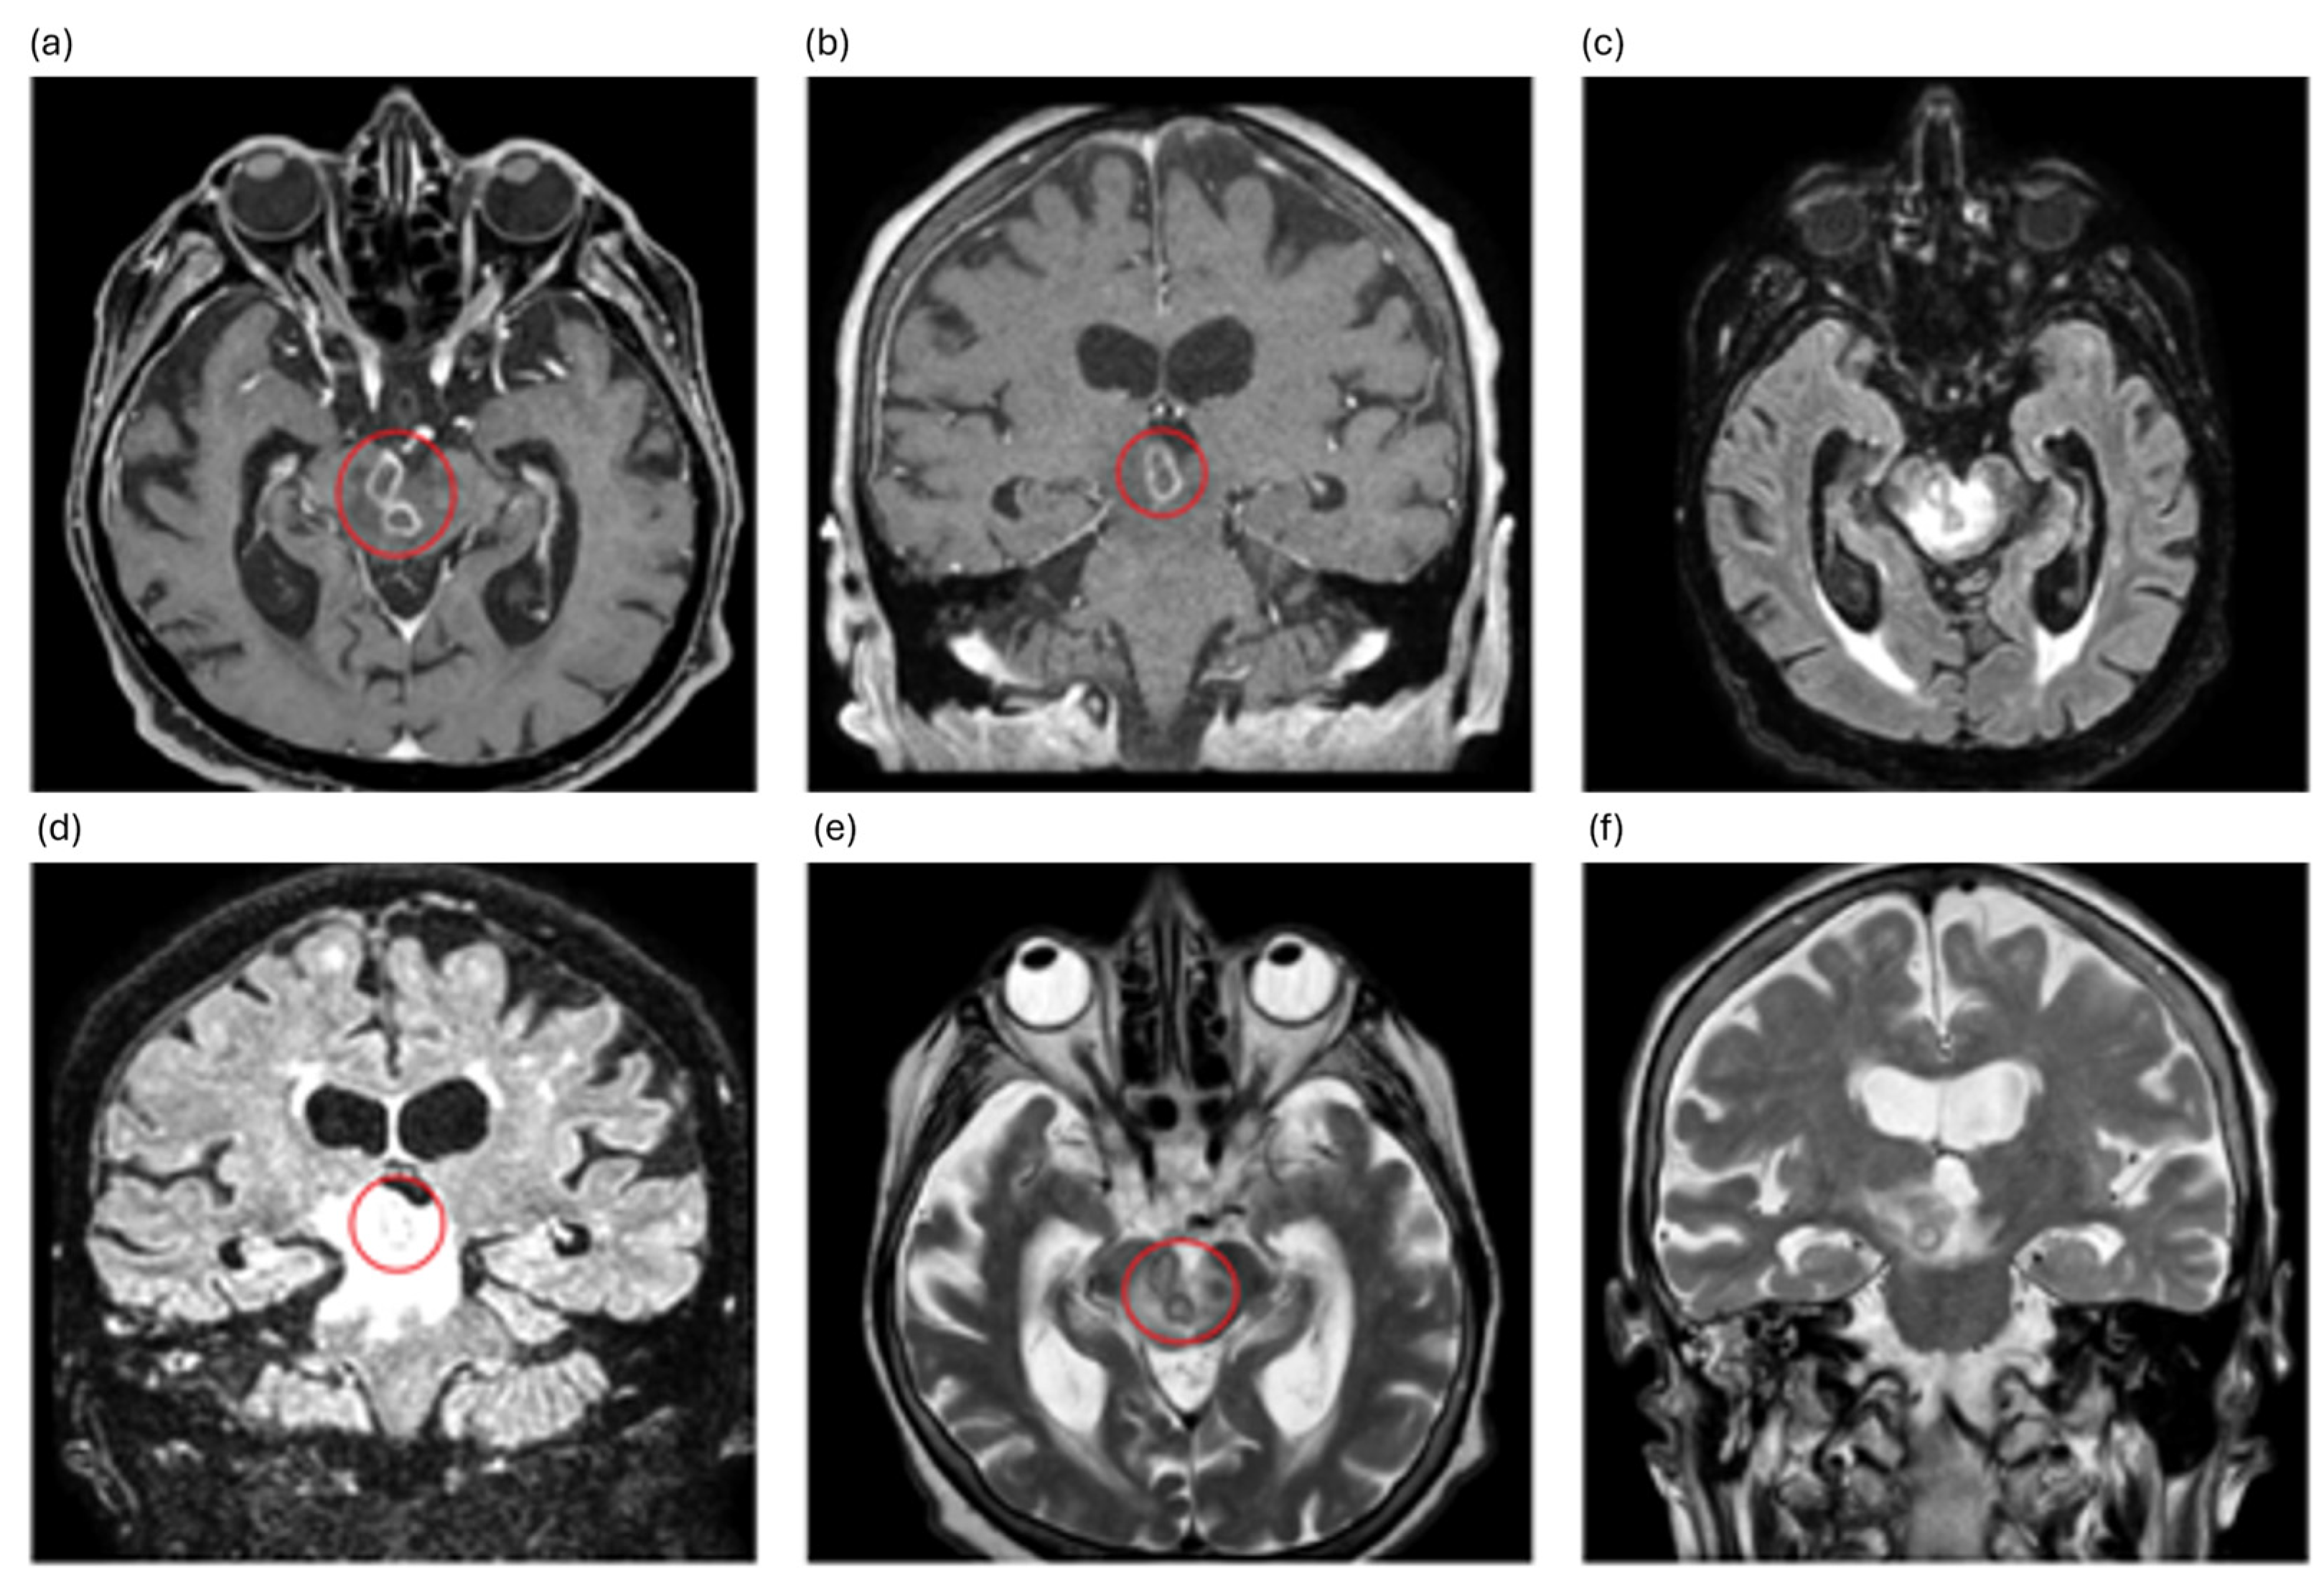

2. Case Description